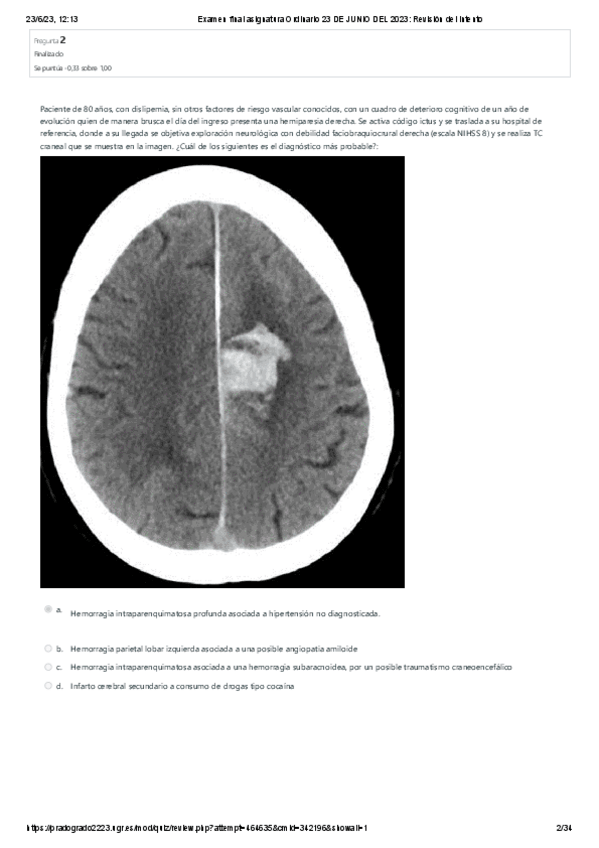

He publicado nuevos examenes de 4º Patología del Sistema Nervioso y Geriatría: EXAMEN-FINAL-NEURO-2023.pdf